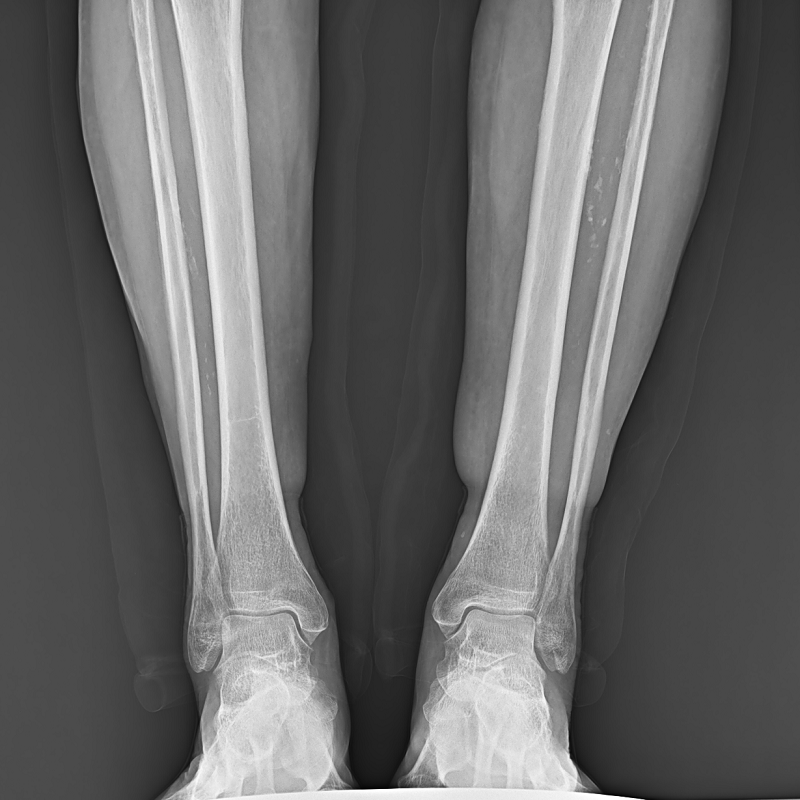

球管及胸片架可大范圍縱向移動(dòng),平板探測(cè)器中心最低離地35cm,輕松滿足膝關(guān)節(jié)、踝關(guān)節(jié)等低位攝影的要求。

● 圖像拼接

系統(tǒng)可以識(shí)別曝光圖像,無需設(shè)置識(shí)別點(diǎn)即完成精準(zhǔn)拼接,呈現(xiàn)大范圍完整影像。